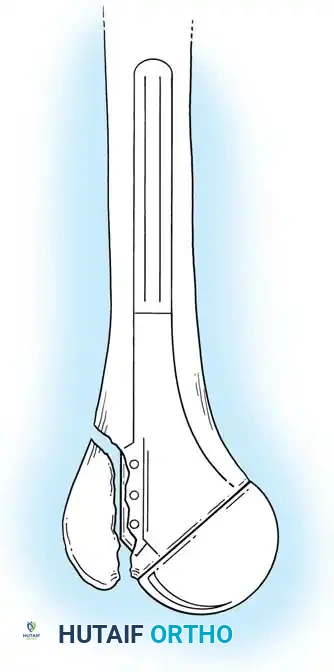

Types of Elbow Arthroplasty

- Linked (Semiconstrained): The humeral and ulnar components are physically connected via a locking pin. This is the workhorse for most Total Elbow Arthroplasties (TEA), especially in cases of ligamentous insufficiency or severe bone loss.

3. Canal Preparation and Implantation

The humeral and ulnar canals are sequentially broached.

- A cement restrictor is placed in both canals.

- Antibiotic-loaded polymethylmethacrylate (PMMA) bone cement is injected in a retrograde fashion.

- The components are inserted, and the articulation is linked using the manufacturer-specific locking pin mechanism.

Surgical Warning: The ulnar component must be inserted with precise rotational alignment. Malrotation will lead to eccentric wear of the polyethylene bushings and early catastrophic failure of the linkage mechanism.